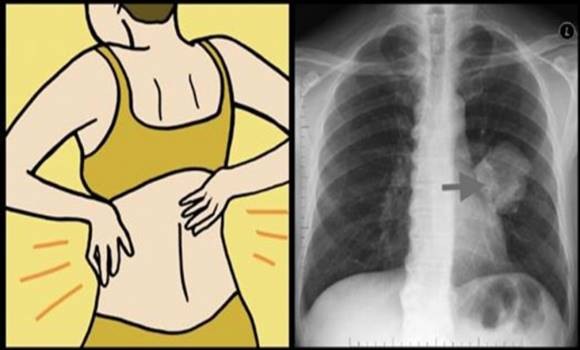

Lung cancer is one of the most serious types of cancer. It is also one of the most dangerous. The main cause of lung cancer remains smoking, but other factors also contribute to its development, such as long-term air pollution or long-term exposure to smoke. Early diagnosis is absolutely crucial in the case of lung cancer. The earlier you detect the cancer and begin to treat it, the greater the chance of recovery. Do not overlook these 10 early symptoms of lung cancer.

How to recognize lung cancer?

- Problems with breathing – after physical exertion or in a stressful situation this is a normal occurrence. If you suffer from shortness of breath often and it occurs, for example, upon waking, it could be a sign of early-stage cancer. Shortness of breath is a symptom of all types of cancer

- Headache – may indicate that the tumor has formed a metastasis to the head and also that the tumor in the lungs presses on the vena cava through which blood moves from the head to the heart. Its compression can cause severe headaches

- Back and shoulder pain – these symptoms are associated with a certain type of cancer that mainly affects women (adenocarcinoma). This type can also put pressure on the ribs and spine

- Severe fatigue – we feel tired even during a cold. However, if you feel tired even when nothing apparently bothers you and you get enough sleep, you should take notice and consult your condition with a doctor

- Depression and mood changes – According to a study by scientists from the University of Oxford, most patients with cancer suffer from depression and anxiety. This can also be one of the early manifestations of the disease

- Persistent cough – if you cannot get rid of a cough even after treatment and you are coughing up blood, you should definitely visit a doctor

- Loss of voice – it can be the result of an infection, smoking, or dehydration. If you treat the loss of voice properly, the problem will subside in a few days. In the event that you do not improve even after three weeks, visit a doctor. Loss of voice can also be an initial sign of a cancerous tumor that has damaged the vocal cords

- Unexplained weight loss – if you suddenly lose weight without changing your eating or exercise habits, see a doctor. Dramatic weight loss bodes nothing good. It may be a sign that your body is consuming nutrients and reserves it has taken in the fight against the disease. There is also a decrease in appetite for food

- Difficulty swallowing – if it is difficult for you to swallow, but you do not suffer from any allergy, infection, or inflammation. It is likely that a tumor is blocking your throat and esophagus

- Chest pain – a tumor in the lungs can also cause pain in the chest, in the back and shoulders